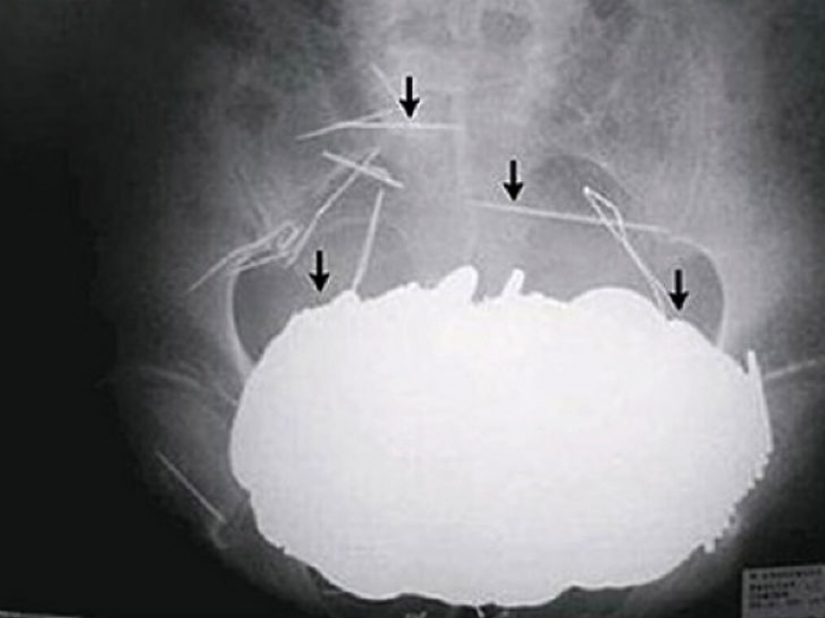

Yes, swallow the silverware is expensive. How about a 78 silver spoons, who swallowed a 52-year-old woman in the Netherlands?